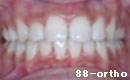

叢生・15歳代・女性

初診時、過度に上下顎に叢生が存在し、向かって左側の側切歯は内側に位置しています。

また、上下顎前歯が前方に傾斜し、口元において口唇の突出感が認められました。

絶えず、口唇が閉じれないためか上顎前歯部に着色(汚れ)が見られます。

治療においては、叢生、口唇部の突出の改善も考え、上下顎小臼歯の便宜抜歯を行い治療を行いました。

治療後、叢生はなくなり、突出していた口元(プロファイル)も改善しすばらしい口元になりました。